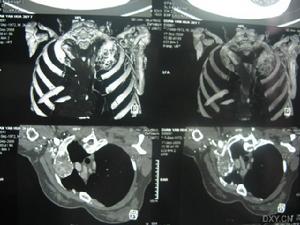

骨膜軟骨瘤1.大體檢查 典型的骨膜軟骨瘤是位於骨皮質外的一個圓形或卵圓形不同大小腫塊。大多數最大直徑不超過4cm,表面有纖維組織構成的包膜覆蓋切面可見腫瘤呈分葉狀為淺藍色或灰白色透明軟骨;其中有黃白色的鈣化點或者條紋腫瘤一般不侵犯軟組織及髓腔。

2.顯微鏡檢查 骨膜軟骨瘤是由透明軟骨小葉組成某些骨膜軟骨瘤,鏡下表現為典型的內生軟骨瘤所見,即細胞小而分散,核緻密,也有一些細胞大而成叢,細胞核不典型或為雙核細胞。腫瘤的邊緣常有大量的薄壁血管和反應性新生骨形成的病灶。在腫瘤生長的邊緣新生骨可以形成一薄殼。病變的基底則為硬化性新生骨,並與骨皮質相連。單憑組織學檢查難以區別軟骨瘤來源於骨膜軟組織。

骨膜軟骨瘤應與骨膜軟骨肉瘤和骨皮質旁軟骨肉瘤相鑑別,但較困難。雖然骨膜軟骨肉瘤病人年齡常較骨膜軟骨瘤病人大,且腫瘤體積較大,但鶒在具體病例中難以區別。應參照X線表現等再具體考慮其診斷。